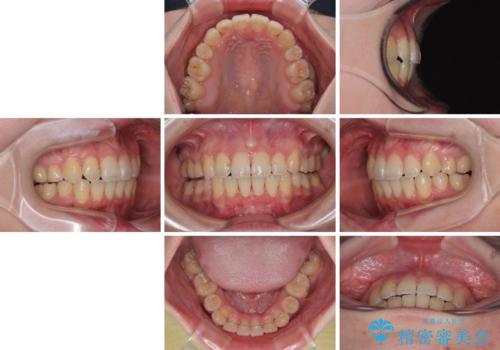

デコボコだらけの歯列をきれいに ワイヤー装置での抜歯矯正治療

予定の2年半を越えてしまいましたが、無事にきれいな口元に仕上げることができました。